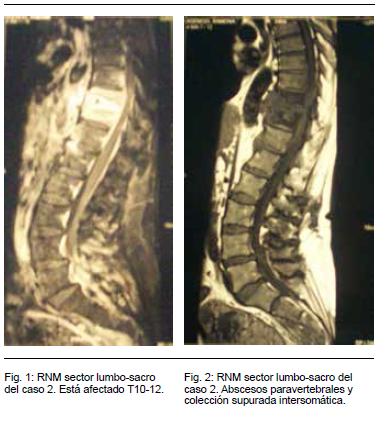

RNM de Columna dorso-lumbo-sacra: discoespondilitis piógena a nivel de T10-T12-L1. Múltiples abscesos paravertebrales y una colección supurada íntersomática, medula con señal hiperintensa, traducción de edema parenquimatoso (Figuras 1 y 2)..

La punción ósea bajo TC sólo se realizó a dos pacientes (casos 2 y 3) siendo ambas negativas (los dos pacientes bajo tratamiento ATB). El escaso número de pacientes en que se efectuó la punción vertebral se relaciona con el alto rendimiento diagnóstico que tuvieron los hemocultivos (100%) y a la dificultad en nuestro medio al acceso rápido a esta técnica, que determinó que no pudiera realizarse previo al comienzo de la antibioticoterapia, lo que condicionó sus resultados. El rendimiento de la punción guiada bajo TC varía entre 60-70% en la mayoría de los estudios. Los HC fueron positivos en mayor porcentaje de lo expresado en otras series.(13) En cuanto a la valoración imagenológica, la RNM de columna fue diagnóstica en 100% de los casos y aportando además datos de la extensión del proceso así como valorando la presencia de complicaciones tanto infecciosas como mecánicas. Los hallazgos de la RNM muestran en todos los casos el compromiso vertebral y en 5/6 la existencia de abscesos paravertebrales: peridurales, del psoas o de otras partes blandas paravertebrales. Destacamos que una paciente permaneció con secuelas de tipo neurológico (paraparesia espástica grado 3) posteriormente al tratamiento completo (caso 2).